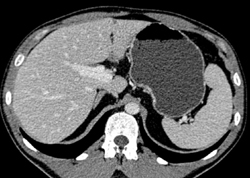

Splenic Hemangiomas